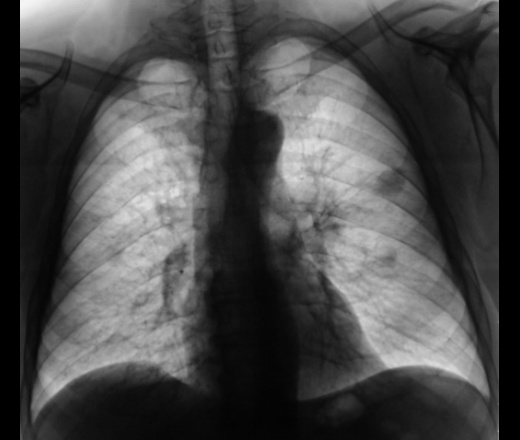

Первая мысль, которая пришла в мою "костно-суставную голову" это метастатическое поражение легких и л\у.

Мы сначала подумали о "тубере". Пациент пролежал неделю в областном учреждении и тубер отвергли.

Затем с учётом скиалогии и отвергнутого тубера выставили "мета" под вопросом, и пациент потопал в ООД, где был обследован, и был выставлен диагноз - "метастазы в легкие". Подтверждено гистологически.

На последних томограммах, на мой взгляд, имелся полный джентельменский набор метаститического процесса. Правда, смущали метастазы с распадом, но такие встречаются и в последнее время довольно часто.

И, все обомлели. Снимки ниже.

Снимки.

Так, какие мнения будут, уважаемые коллеги, по поводу патологического процесса?

Пациент ничего не пил. Ему даже не отважились провести "химию", что-то весьма серьёзное с сердцем. Психологически он уже был готов к отходу в мир иной. Случай сегодняшний, с женой больного истерика...

Я пока цепляюсь за правую верхушку. Сегодня звонил в областную контору, ему делали КТ, попросил, чтобы глянули архивчик. Говорят, что такой "хрени" на правой верхушке не было. Сам в сомнениях и размышлениях, может коллеги чего посоветуют.

- аспергиллёз?..

М.б. лимфома/лейкоз, в легких инфильтрация, а не mts, и пациент вошел в ремиссию?

Конечно, все может быть, все может статься, но сеялось не единыжды и не на одном виде сред. К тому, же без соответствующего лечения, излечение от этой нозологии весьма проблемно....

В настоящее время, кровь - рядом с нормой, хотя, когда ООД, выставил соответствующий диагноз, говорили, что кровь типичная, именно, для онкологического процесса.

Афигеть. Рак рассосался. Что значит не лечили ))))))

Ну, сейчас, и ООД и ОПТД чувствительно "сели на копчик", по всей видимости областные "тубари" заберут, хотя-бы для "окончательного диагноза"...